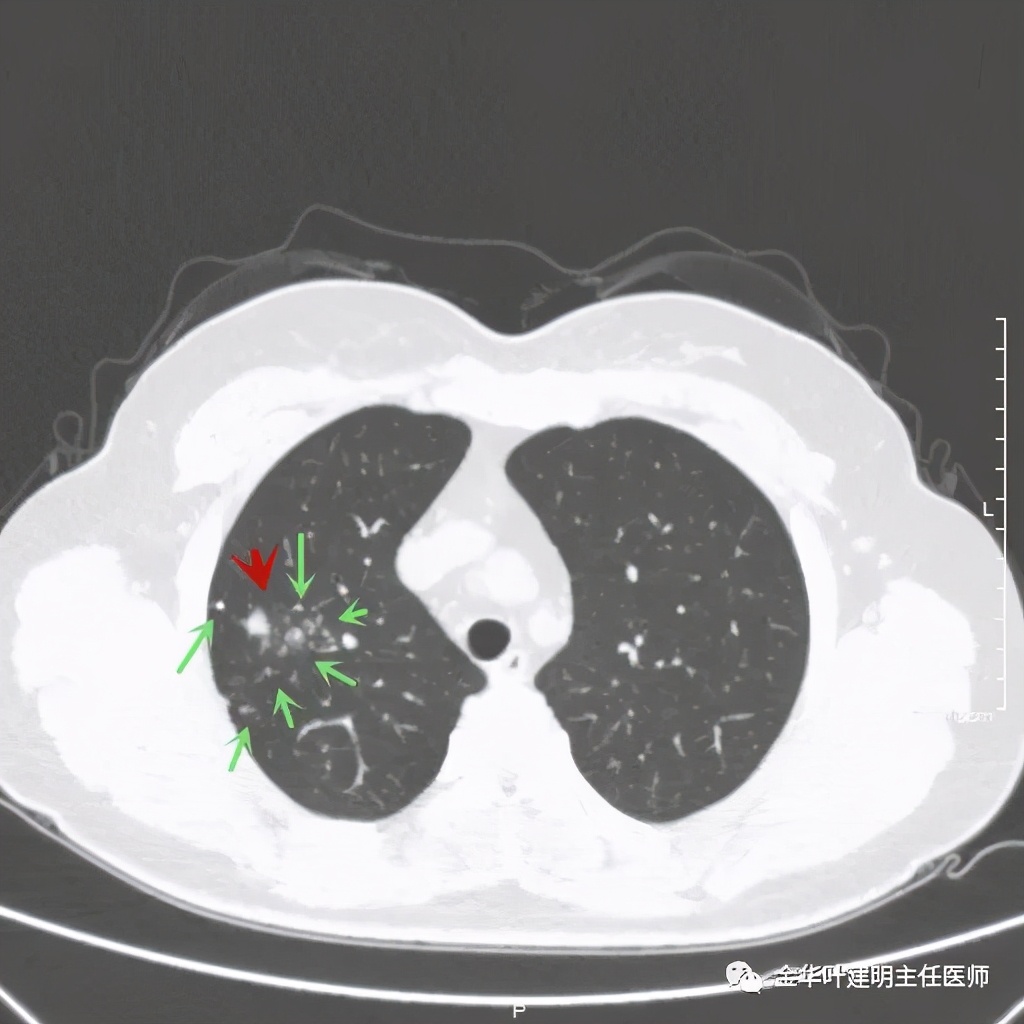

绿色箭头示病粉旁边有卫星灶,而且密度都高,主病灶也是实性

病灶边散在多发微小实性与似磨玻璃的微小结节

病灶附近不清爽